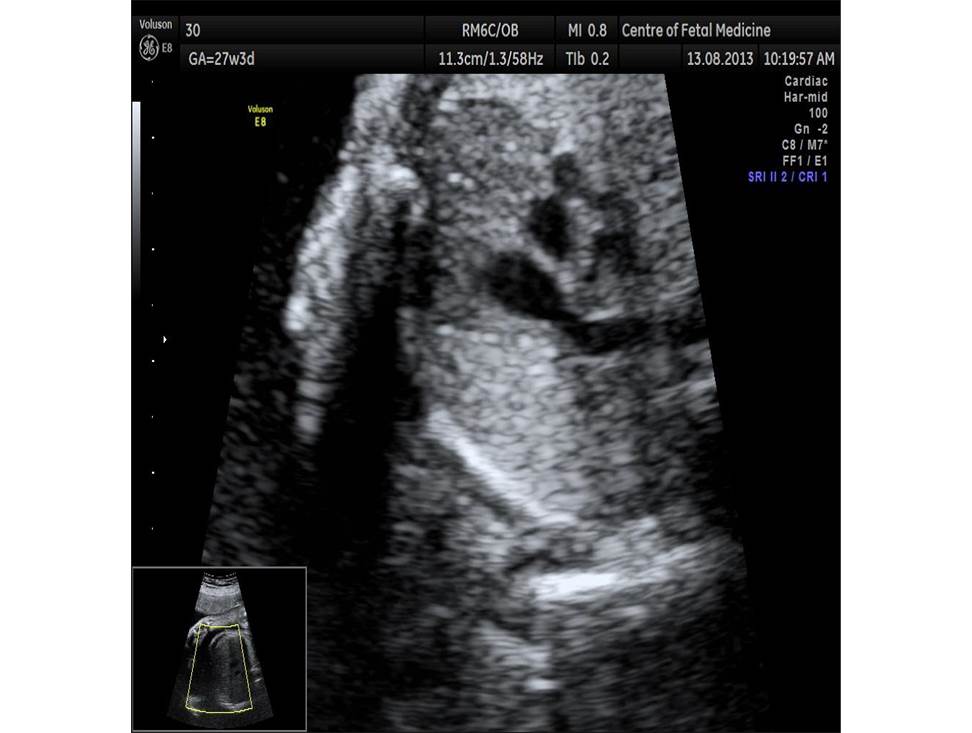

Вопрос 1

Проанализируйте изображения плода в 27 недель, установите диагноз и дальнейшую тактику ведения беременности